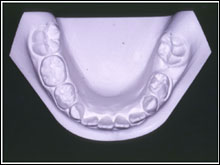

乳歯がなければ!

まわりの乳歯の移動、後継永久歯の変化

乳臼歯の骨性癒着による咬合異常

4. 下顎左側第一大臼歯の著しい近心傾斜

5. 下顎左側第二乳臼歯の埋伏低位と後継永久歯胚の位置異常